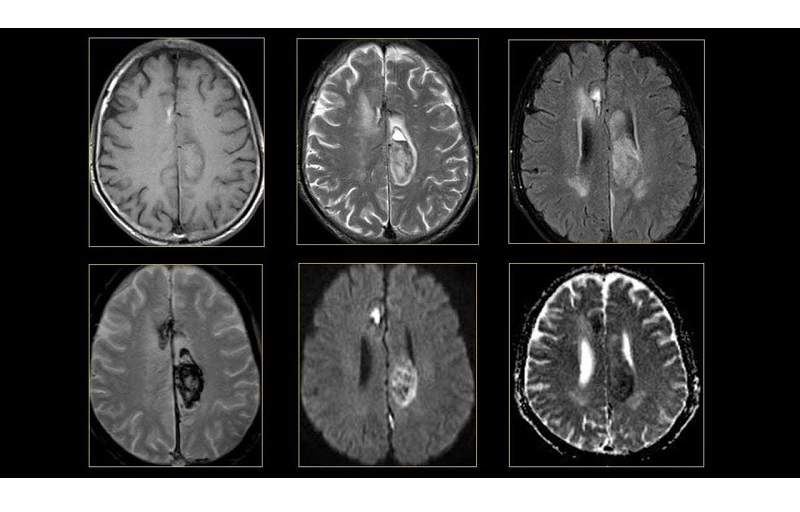

Máy chụp MRI là một công cụ tiên tiến trong y học, giúp bác sĩ quan sát chi tiết các cơ quan và cấu trúc bên trong cơ thể mà các phương pháp như X-quang hay CT không thể hiển thị rõ ràng.

Nhờ khả năng cung cấp hình ảnh sắc nét, MRI được ứng dụng rộng rãi trong chẩn đoán nhiều bệnh lý như tim mạch, đột quỵ, rối loạn cơ – xương và ung thư. Đây là phương pháp chẩn đoán an toàn, không đau và không xâm lấn, mang lại trải nghiệm thoải mái hơn cho người bệnh.

– Hình ảnh sắc nét, chi tiết: Đặc biệt hiệu quả trong việc hiển thị mô mềm, giúp phát hiện tổn thương mà các phương pháp khác có thể bỏ sót.